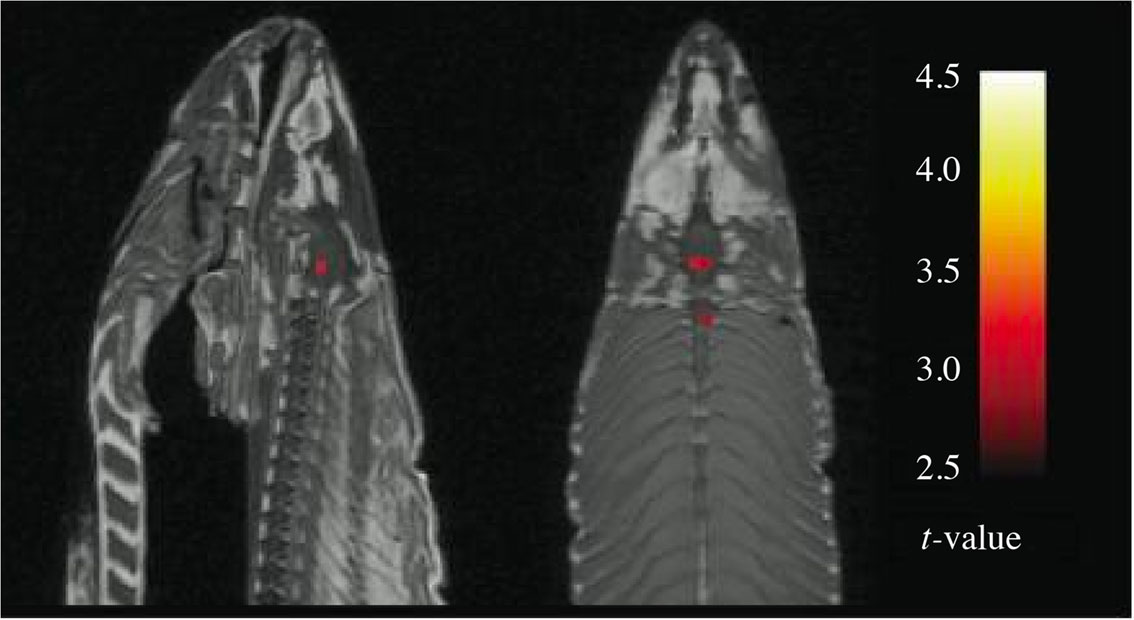

Jo Røislien skriver at bildet av den døde laksen viste «tre statistisk signifikante prikker» (1).

Menes at bildet viste tre områder hvor det før og etter stimulering var en forskjell i signalstyrke (longitudinell studie), eller kun en forskjell i signalstyrke mellom forskjellige anatomiske områder (tversnittstudie)? Presiseringen er helt avgjørende for å vurdere dette funnet. I en tversnittstudie kan en forskjell i prikkene vise reelle kjemiske forskjeller, også hos en død laks.

Begrepet «statistisk signifikant» er vanligvis knyttet til en p-verdi. I dette tilfellet synes imidlertid ordet «signifikant» å være knyttet til en t-verdi. T-verdier er en form for kvantifisering av forskjeller, altså et litt komplisert effektestimat som er uavhengig av antall observasjoner. P-verdien derimot, er sterkt avhengig av antallet slik at ubetydelige forskjeller blir signifikante bare antallet observasjoner er stort.